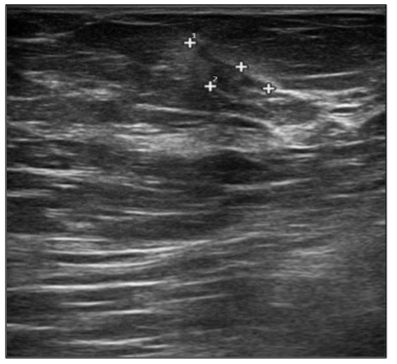

In September 2019, a 69-year-old woman presented to the emergency department of the University Hospital Città della Salute e della Scienza – Turin (Italy), reporting extreme fatigue and dyspnea. She had no comorbidities except for a medical history of papillary thyroid cancer, treated with thyroidectomy and radiotherapy 13 years before. Her complete blood count revealed anemia, thrombocytopenia and leukocytosis (Hb: 7.8 g/dL, PLT: 37 × 109/L, WBC: 45 × 109/L), while her physical examination was normal. The bone marrow smear showed 84% of blasts with myeloid immunophenotype (CD45, CD13, CD33, HLA-DR, lysozyme, CD36, CD64, CD11bc, partial CD14, and CD4 positive), molecular biology showed NPM1 mutation and FLT3-ITD positivity, while karyotype was normal (46, XX, 20/20). Consequently, a diagnosis of FLT3-ITD+ and NPM1 mutated t-AML was made. Induction chemotherapy was started with CPX-351 (liposomal daunorubicin 44 mg/m2 and cytarabine 100 mg/m2), obtaining CR with a 3-log NPM1 reduction (0.177). She was consolidated with CPX-351 (liposomal daunorubicin 29 mg/m2 and cytarabine 65 mg/m2 day 1 and 3), remaining in CR with persistent low level of measurable residual disease (MRD), NPM1 0.34. Meanwhile, we found a suitable HLA matched donor, but the patient refused the transplant procedure. Thus, we decided to start off-label azacitidine as maintenance therapy (50 mg/m2 subcutaneous daily for 5 days, every 28 days). Maintenance therapy was globally well tolerated, and the patient experienced only positivity for COVID-19 without need of hospitalization or additional care. She remained in CR with persistent MRD in BM (NPM1 0.044 after 12 cycles). During the fifteen course (May 2021), we found a palpable right mammary nodule on physical examination, confirmed on ultrasound, with a diameter of 18 x 11 mm. We stopped azacitidine and we promptly biopsied the nodule with a diagnosis of breast infiltration by AML blasts carrying the NPM1 mutation. CT scan and PET of chest, neck and abdomen were negative, and BM evaluation showed 1% blasts, with NPM1 0.044. The FLT3-ITD mutation resulted positive on breast cells while negative on medullary blasts. Thus, concluding for extramedullary relapse of AML FLT3-ITD mutated, we decided to start gilteritinib as single agent, at a dose of 120 mg daily. After 30 days, mammary ultrasound showed a reduction in diameter of the nodule, and in 4 months, the lesion has completely disappeared. The PET scan performed after 5 months of treatment was persistently negative and confirmed the absence of other uptakes. BM re-evaluation showed no blasts, with NPM1 0.006. Today, after 44 months of treatment, our patient is still in CR without signs of clinical and radiologic relapse. We continue monitoring her MRD status every two months on peripheral blood, as shown in table 1. Globally, therapy has been always well tolerated. In January 2024, we had to stop gilteritinib for 28 days due to pyelonephritis and sepsis treated with broad spectrum antibiotics. During this time, she remained in complete remission without any sign of relapse. After some months, in September, our patient has undergone exeresis of basal cell carcinoma, without complications and without need of stopping gilteritinib.